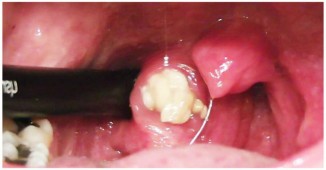

იმისთვის, რომ შევინარჩუნოთ ორგანიზმის საერთო ჯანმრთელობა მრავალი წლით, აუცილებელია პირის ღრუს შესაბამისად მოვლა. მეცნიერების მტკიცებით, პირის ღრუს..

პირის ღრუს ჰიგიენის დაცვა კბილის პასტის, ჯაგრისისა და სპეციალური ძაფის გამოყენებით ყოველთვის სასურველ შედეგს ვერ იძლევა...